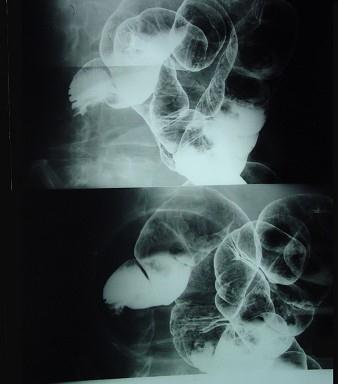

问题 男,70岁,右下腹胀,腹痛,腹泻,影像检查如图,最可能的诊断是 ( )

选项 A、结肠结核 B、结肠淋巴瘤 C、结肠癌 D、结肠套叠 E、结肠克隆恩病

答案 C